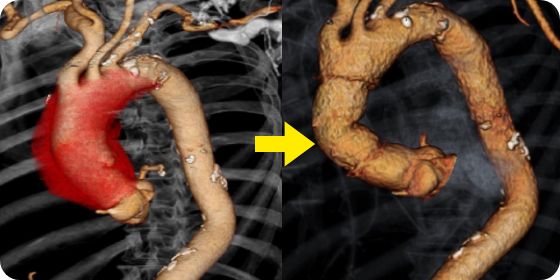

大動脈瘤は、偶発的に診断されることが多いですが、一定のサイズを超えると破裂する可能性があり、破裂をきたした場合の死亡率は80%以上とされ、破裂前の治療が大事になります。治療法は、人工血管置換術とステントグラフト内挿術があります。

胸や腹部を開けて瘤を完全に切除し、人工血管に取り替える手術です。

全身麻酔が必要で体への負担はありますが、瘤を取り除くため確かな治療効果が期待できます。

胸部大動脈瘤に対して施行したステントグラフト内挿術